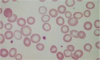

Here…which cells demonstrate a low MCHC & which demonstrate a high MCHC?

the ones that look less pink–>low MCHC–>defective synthesis of hemoglobin

the ones that are super pink & spherical–>high MCHC–>hereditary spherocytosis